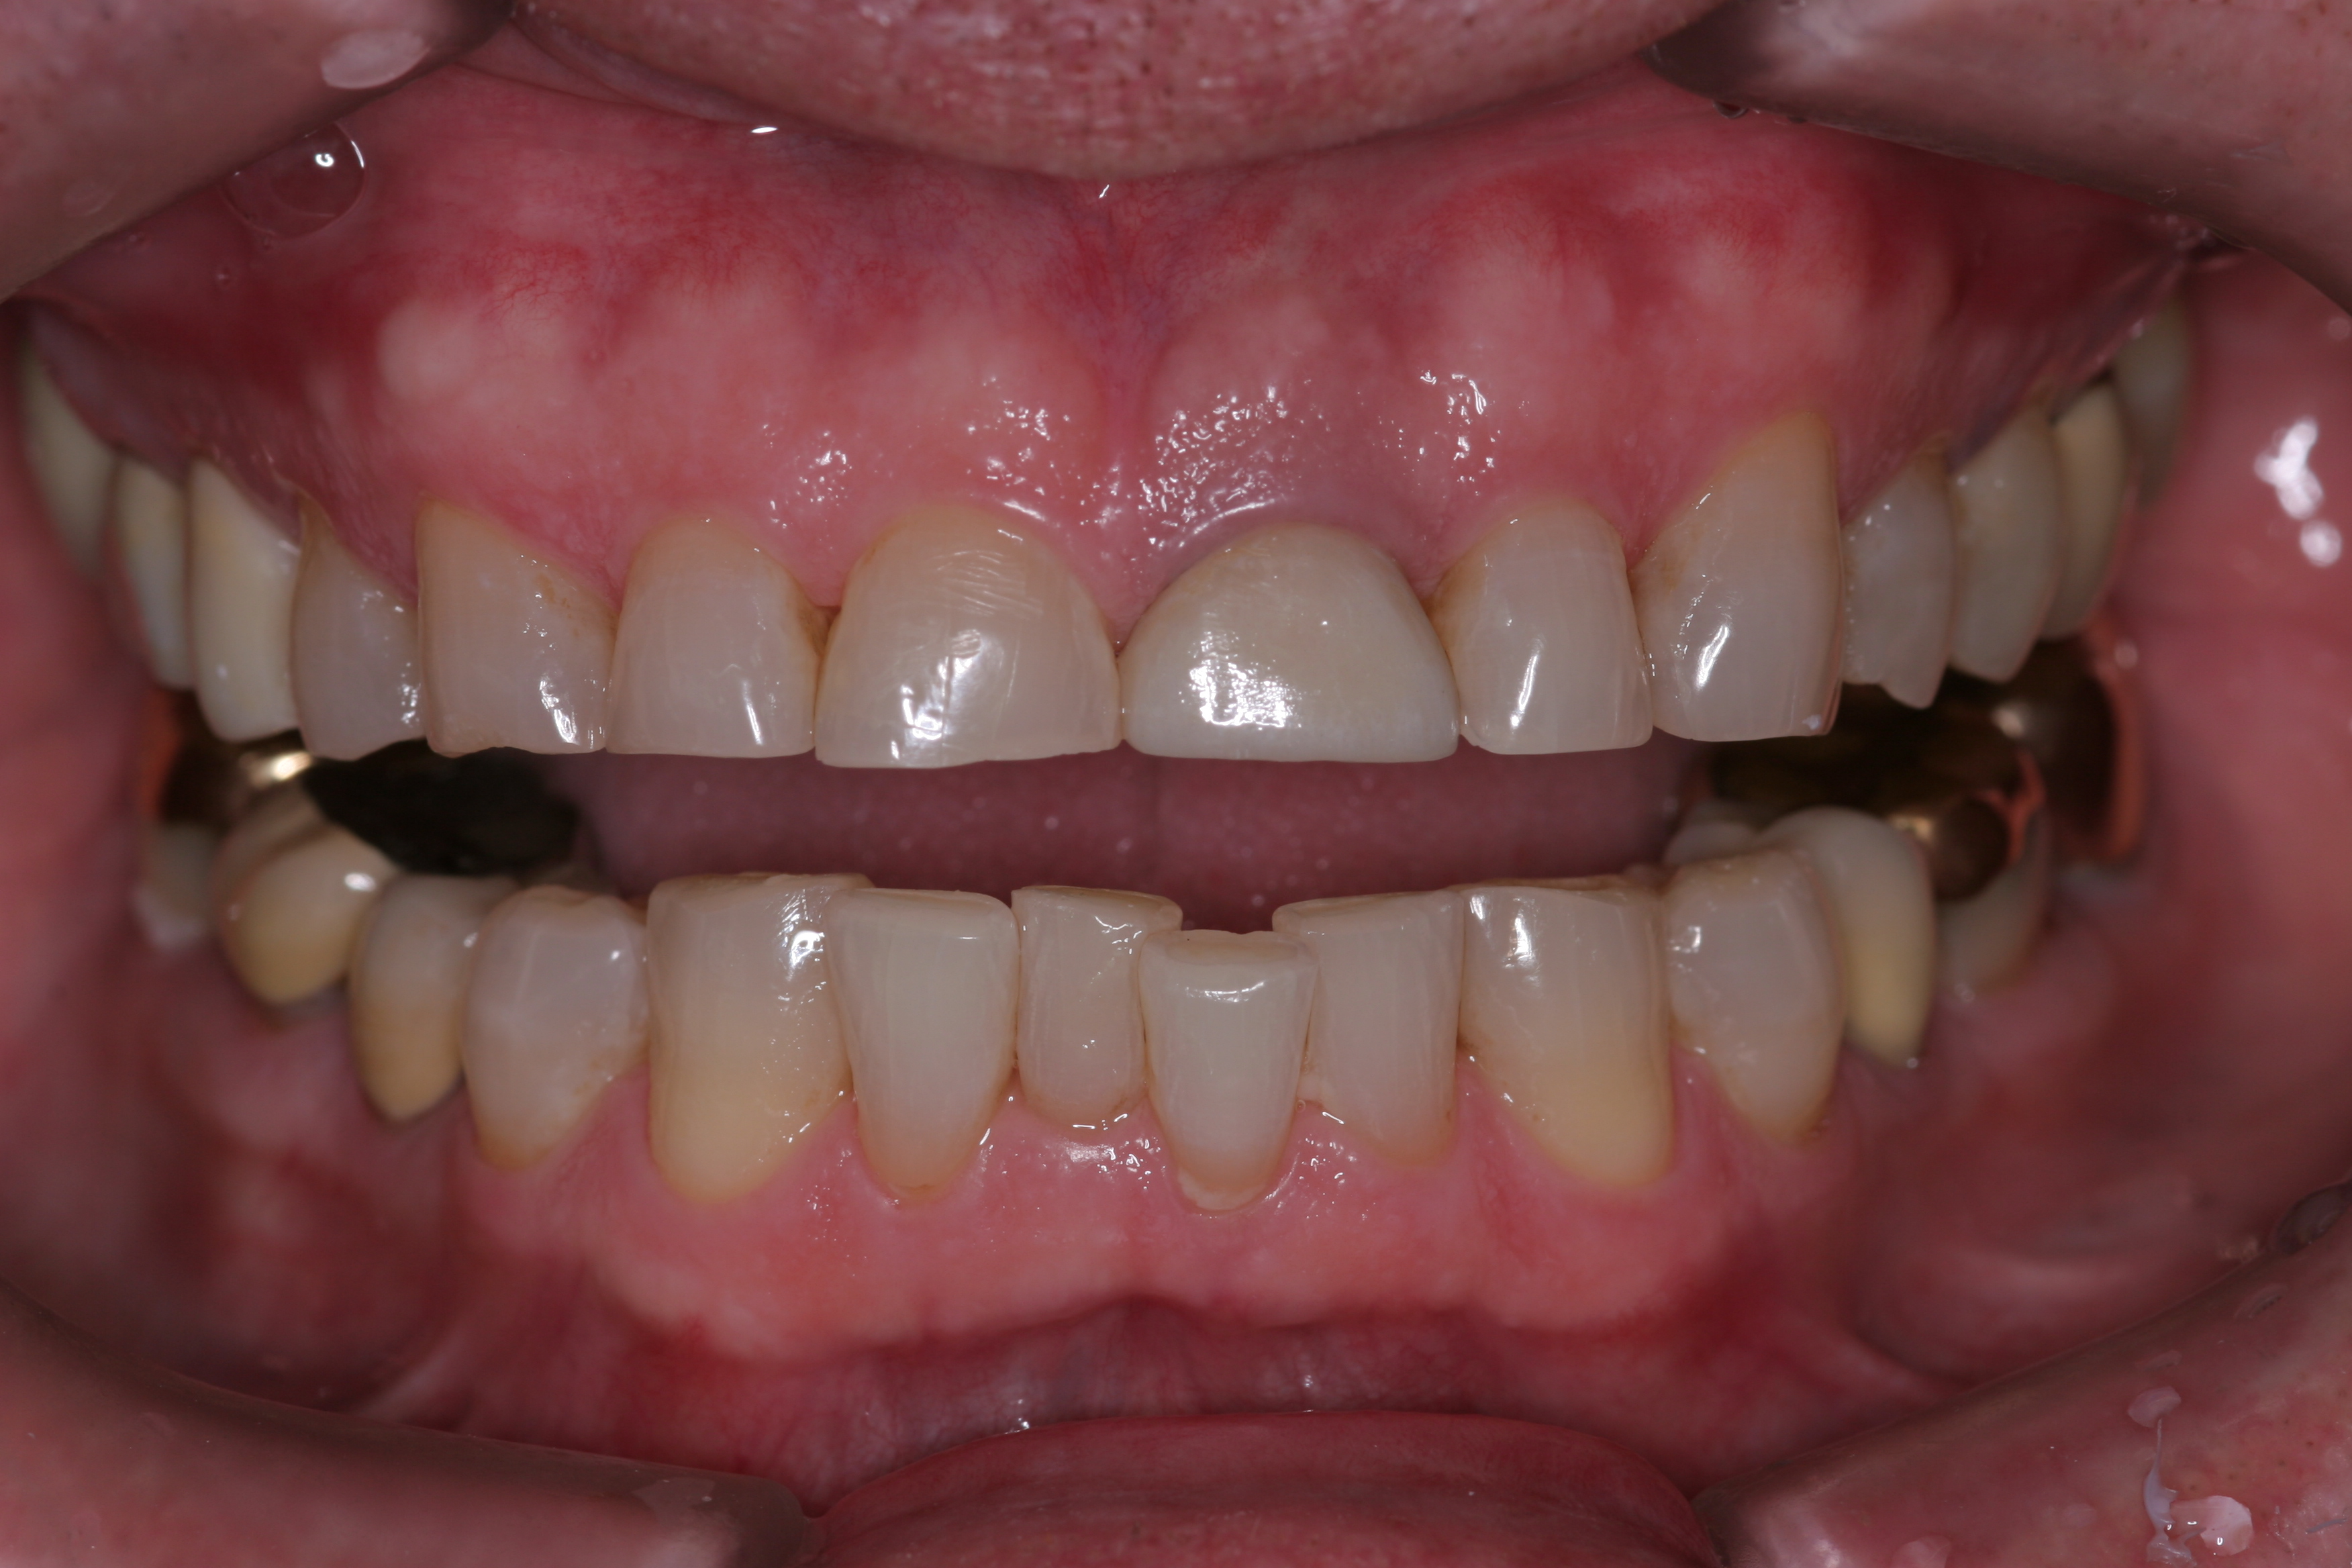

(11.) A patient presented with advanced generalized wear of her anterior teeth, and was displeased with their overall appearance because of their color and wear.

Figure 11

(12.) A patient presented with advanced generalized wear of her anterior teeth, and was displeased with their overall appearance because of their color and wear.

Figure 12

A patient presented with advanced generalized wear of her anterior teeth (Figure 10 and Figure 11). She was displeased with their overall appearance because of their color and wear (Figure 12). A complete examination was performed, revealing instability in her temporomandibular lateral poles bilaterally, sore muscles of mastication, advanced wear, a CR/MIP discrepancy, and loss of her anterior guidance due to the wear. Although the topic is beyond the scope of this article, the patient was also screened for possible sleep apnea. This included an evaluation of the Mallampati score, previous sleep therapy evaluation or treatment, snoring history, an evaluation of her neck size, her weight status, and the presence of the tonsils and their size. In every case, if this clinician suspects airway obstruction to be playing a role in tooth wear issues, the patient is referred to a sleep physician. The patient in this case displayed few apnea risk factors, and the patient’s anterior wear facets fit together like a “lock and key” pattern seen in parafunctional activity. Splint therapy was initiated to stabilize the joints and muscles. A repeatable CR position was verified through load testing. At this point diagnostic models, photographs, a CR bite record, and a facebow were taken and recorded.